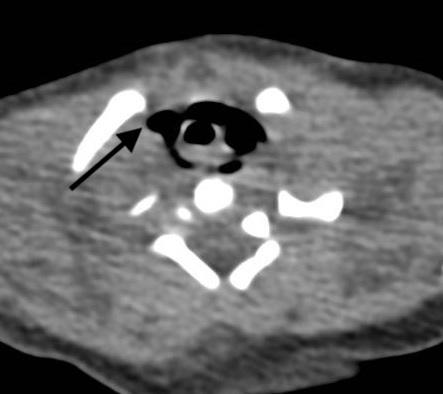

Figure 3

Case 1: CT scan in axial view at the upper thoracic inlet showing pneumomediastinum (arrow) from possible perforation of the upper pouch.